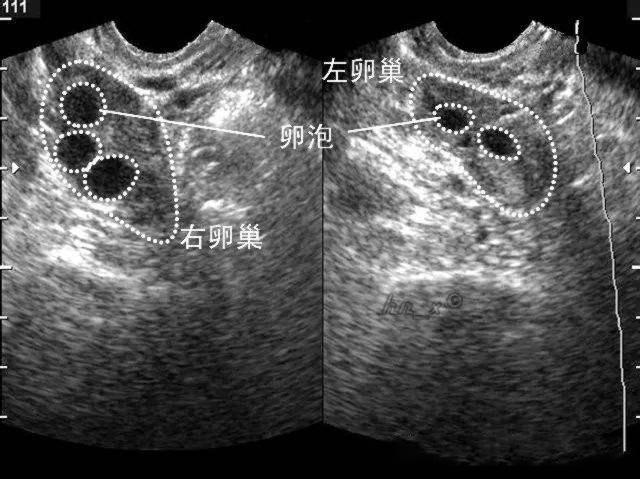

其目的是观察卵巢内卵泡的生长情况,大小和形态,及子宫内膜的情况

同时还能测出优势卵泡的大小,子宫内膜的厚度等

从图中可见:女性月经周期中激素水平,卵泡大小,体温,子宫内膜都在变化